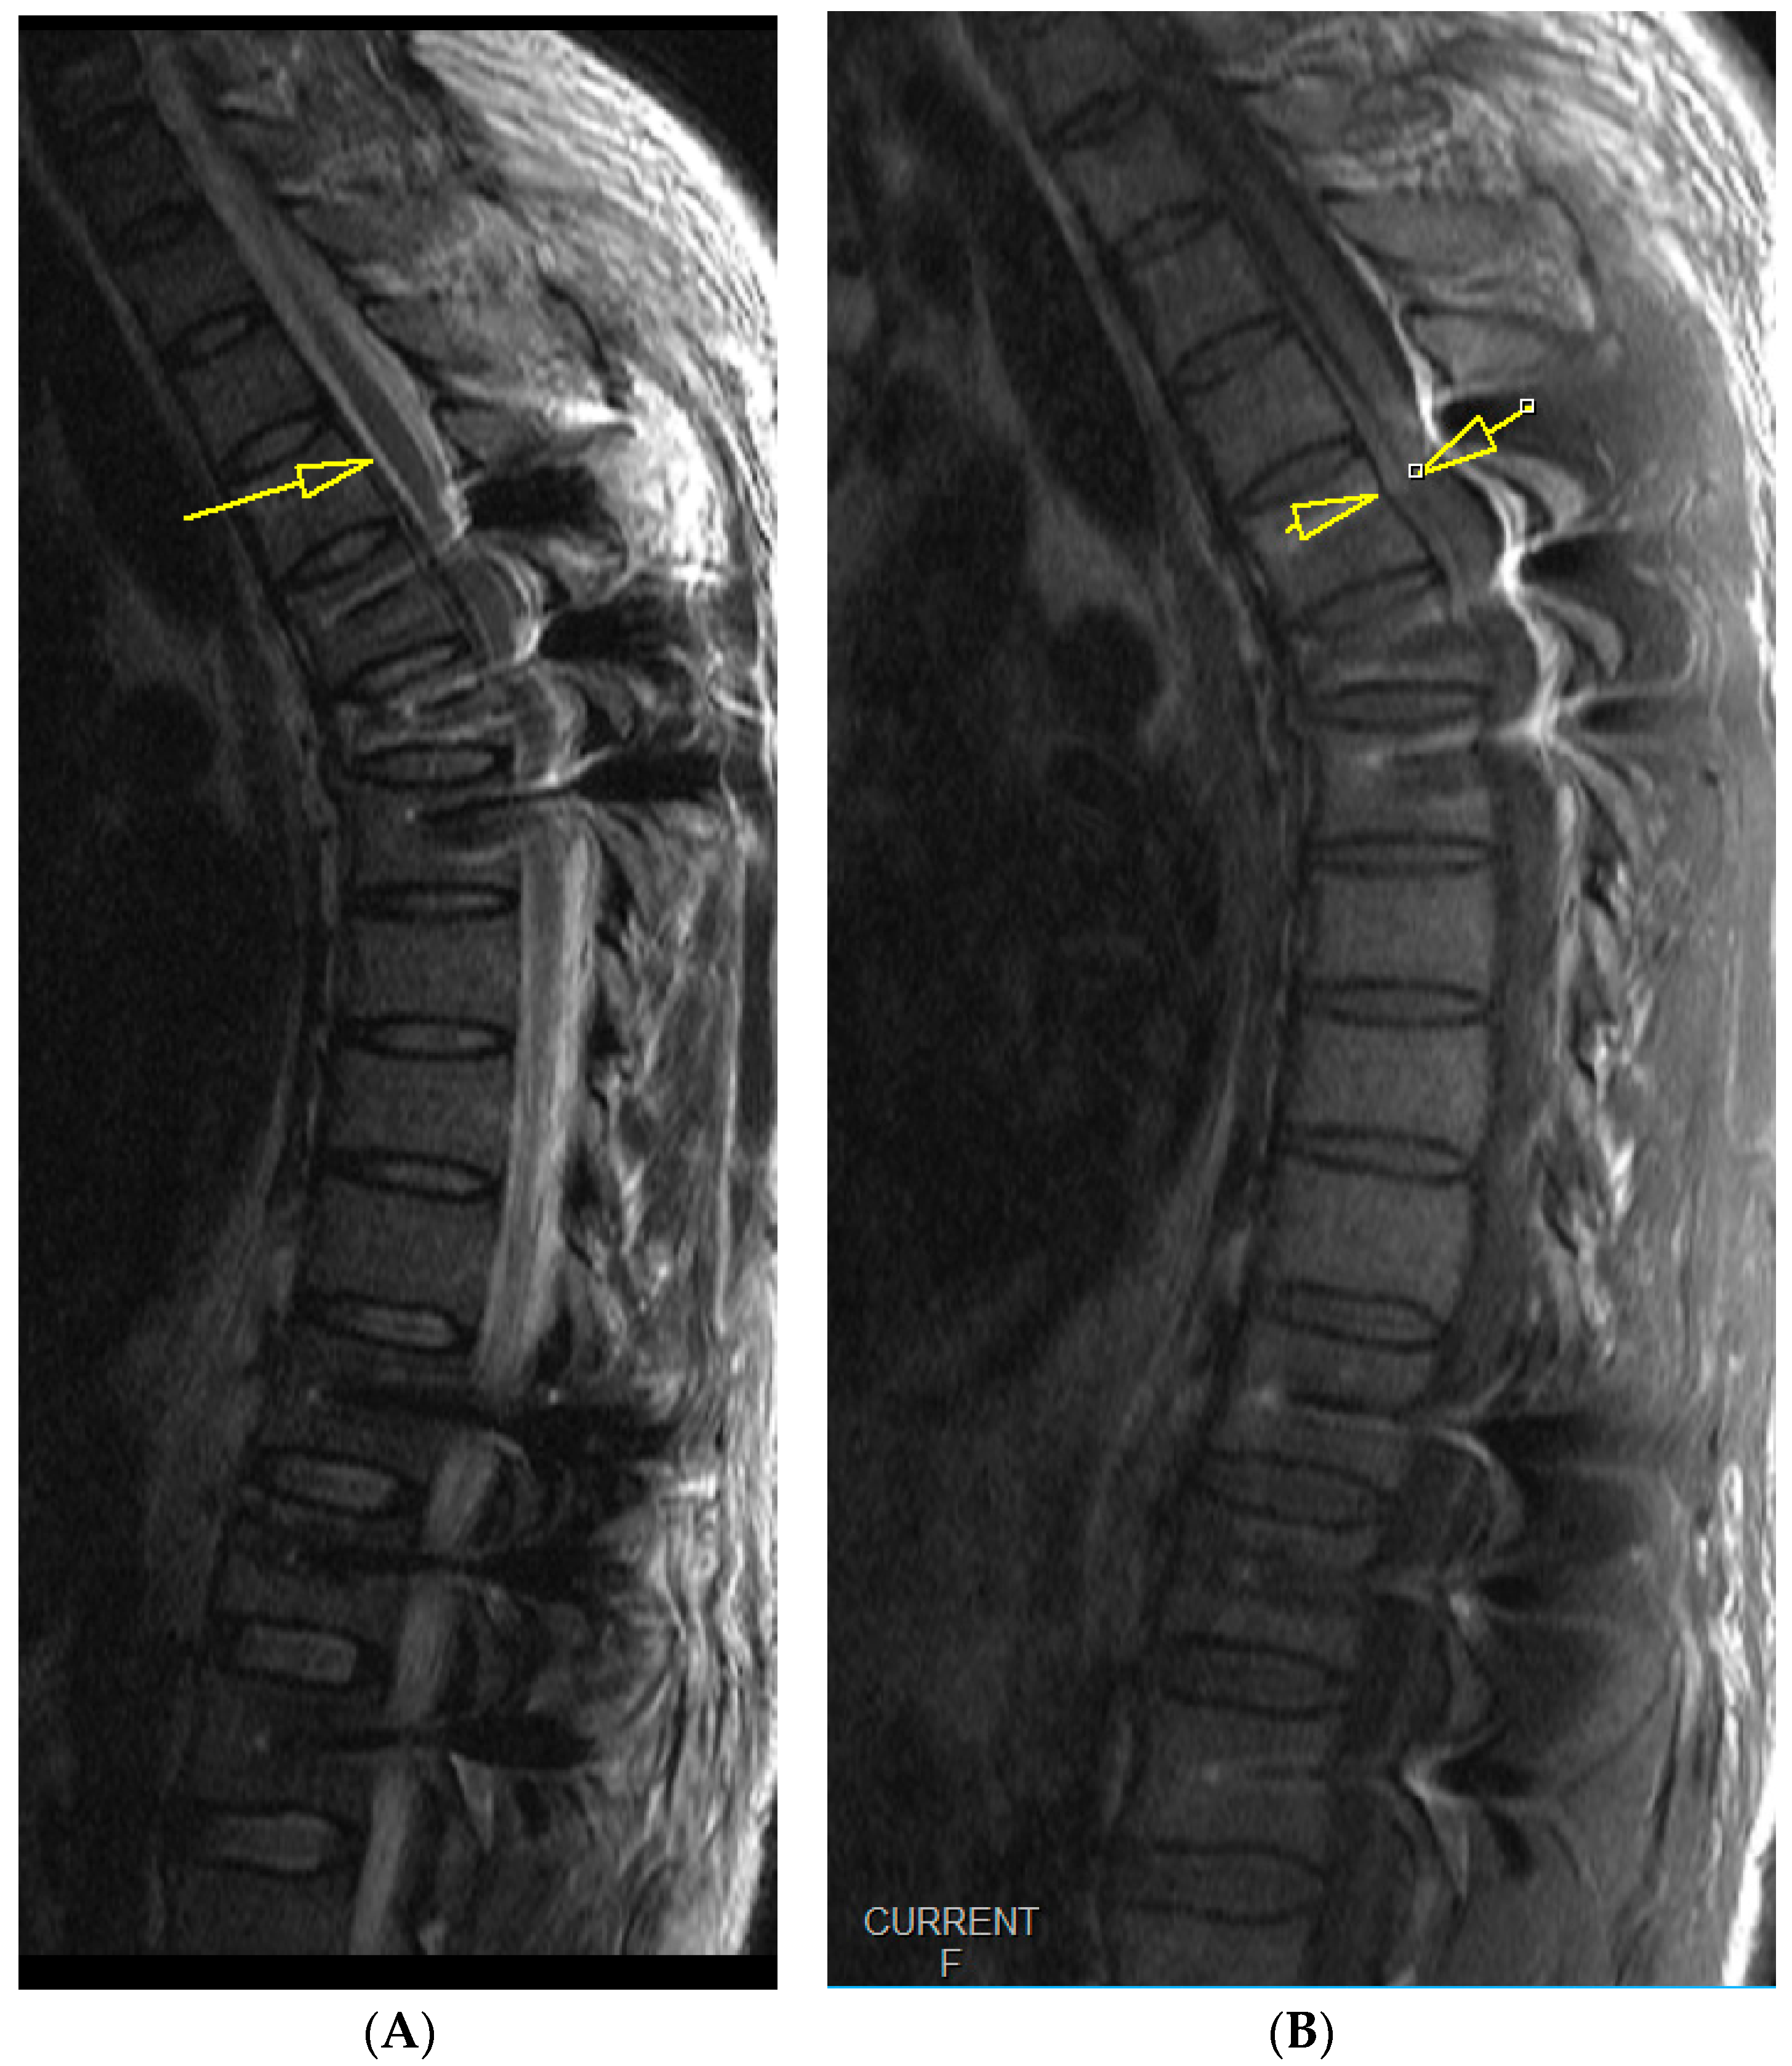

2. Case Report